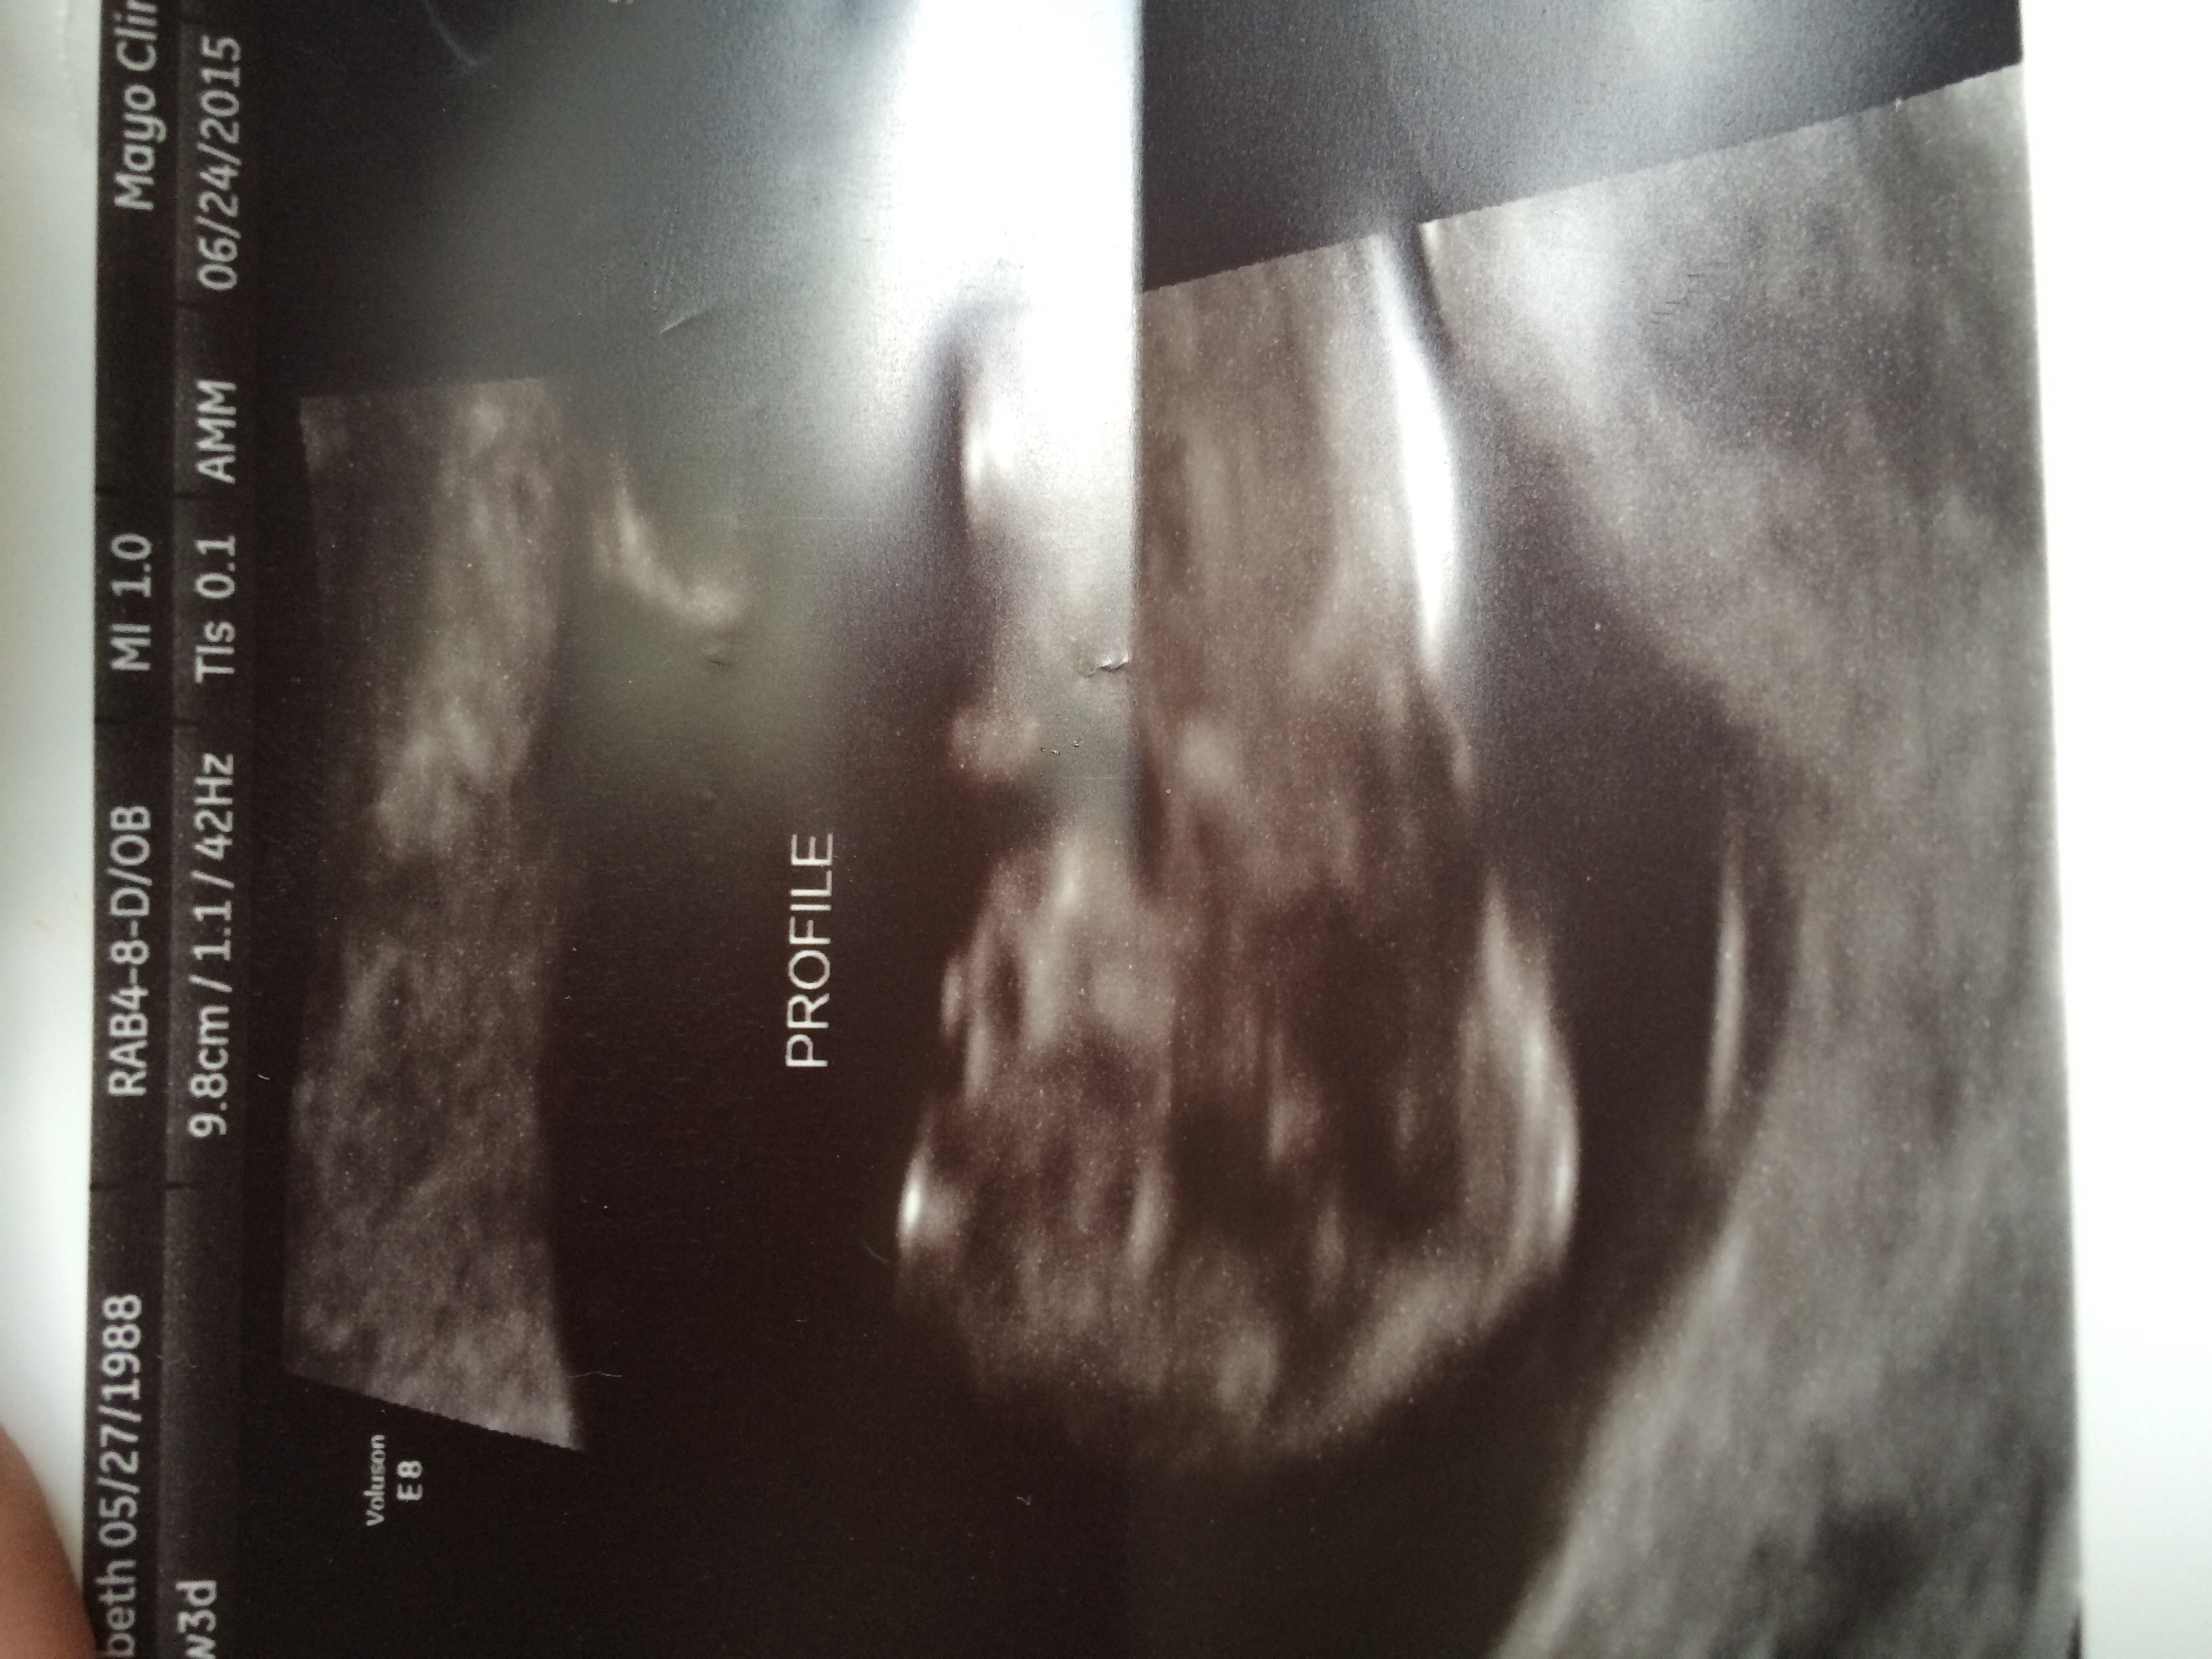

I have been slowly trying to figure out this website for the past few weeks. I am currently 14wk 1d pregnant with our first child. My husband and I have been married for 3 years this September. We are so excited to become parents. I live in Southeastern Minnesota and work as an RN at the hospital there. I love being a nurse but find this whole pregnancy somewhat foreign and an exciting learning experience. I look forward to getting to know you all. Happy Monday!